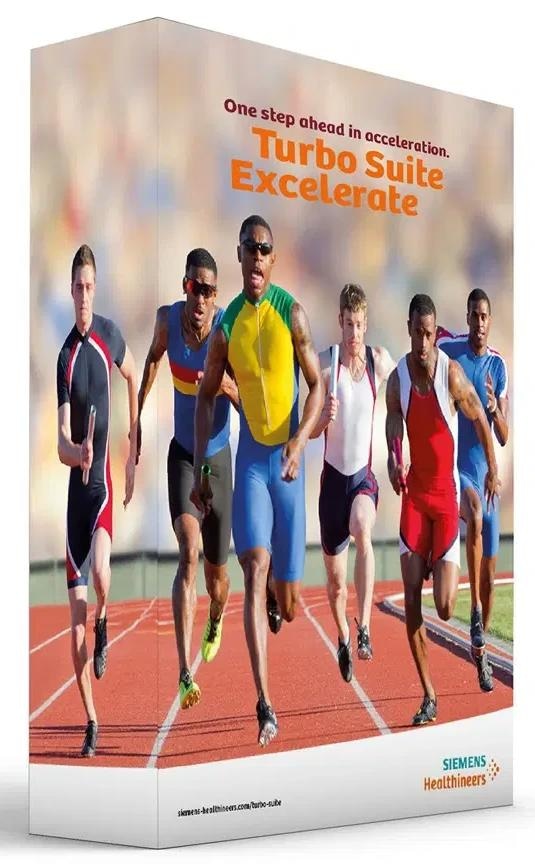

Turbo suite

The new Turbo Suite acceleration packages allow for up to 50% faster clinical routine evaluations.

Embrace true 3T productivity with Turbo Suite and myExam Companion

The MAGNETOM Vida embraces genuine 3T productivity, making quick scan times and push-button examinations clinical realities. The proprietary Turbo Suite is at the heart of its exceptional acquisition speed: Disruptive acceleration technologies (e.g., Simultaneous Multi-Slice and Compressed Sensing) shorten clinical MRI tests across the board while maintaining exam quality.